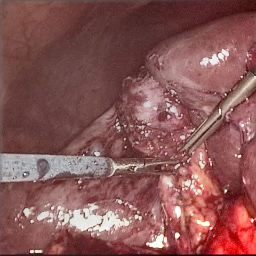

Refer to caption (a) Input Refer to caption (b) DIACMPN Refer to caption (c) Desmoke-LAP Refer to caption (d) PFAN Refer to caption (e) MITNET Refer to caption (f) Salazar Refer to caption (g) Dehamer Refer to caption (h) Ours Refer to caption (i) Target

Figure 2: Comparison of different methods on the DesmokeData dataset.

IV-C2 Qualitative Analysis

Figures 3 and 2 provide a visual comparison of the desmoking results on challenging images from the test sets. The visual results corroborate our quantitative findings. DCP not only fails to remove the dense smoke but also introduces severe color distortion. CNN-based methods like FFA-Net and MSBDN successfully remove a large portion of the smoke but tend to either leave behind a thin layer of residual haze or over-smooth the image, losing critical textural details of the tissue and surgical instruments. The Transformer-based methods, DehazeFormer and PFAN, produce significantly better results by restoring more details. However, they can sometimes struggle with non-uniform smoke distribution, resulting in regions with unnatural brightness or minor artifacts.

In stark contrast, our RGA-Net generates visually superior results that are remarkably close to the ground-truth images. It effectively removes even the densest plumes of smoke while simultaneously preserving fine-grained details, such as blood vessels, tissue textures, and reflections on surgical tools. Furthermore, the color and illumination of the restored scene appear more natural and consistent, which is a direct benefit of our model’s ability to handle both local and global features through its hybrid attention and cross-gating mechanisms. This enhanced visual clarity is crucial for improving the surgeon-robot interface in real-world clinical applications.